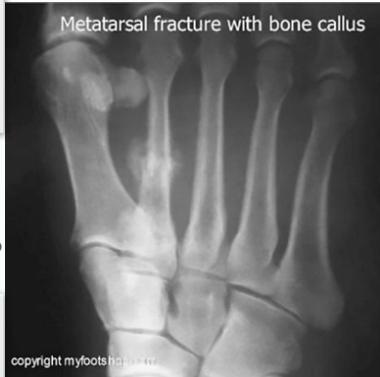

- Stress fracture:

- Histopathology may be confused with osteosarcoma?